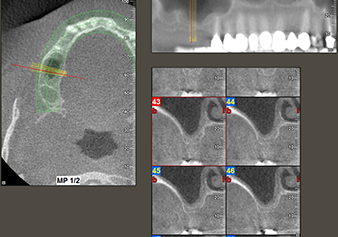

A 49-year-old female patient, a non-smoker and with nothing remarkable in her general medical history, was referred to our oral surgery practice for surgical extraction of tooth 16 and subsequent implantation. After the extraction, the patient experienced mild sinusitis trouble with the resultthat we initially waited six months before carrying out the measure. The residual bone height at the planned implant position measured 3-4 mm (Fig. 1 and 2).

Fig.2: The DVT shows adequate dimensions in each of the axial (left), lateral (top) and transverse views (right). The maxillary sinus membrane is still slightly thickened.